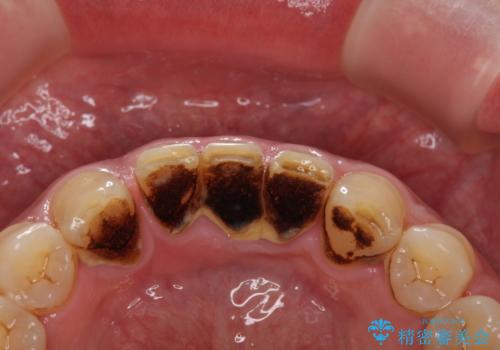

人生で初めて歯のクリーニング〔PMTC〕

担当医 歯科衛生士